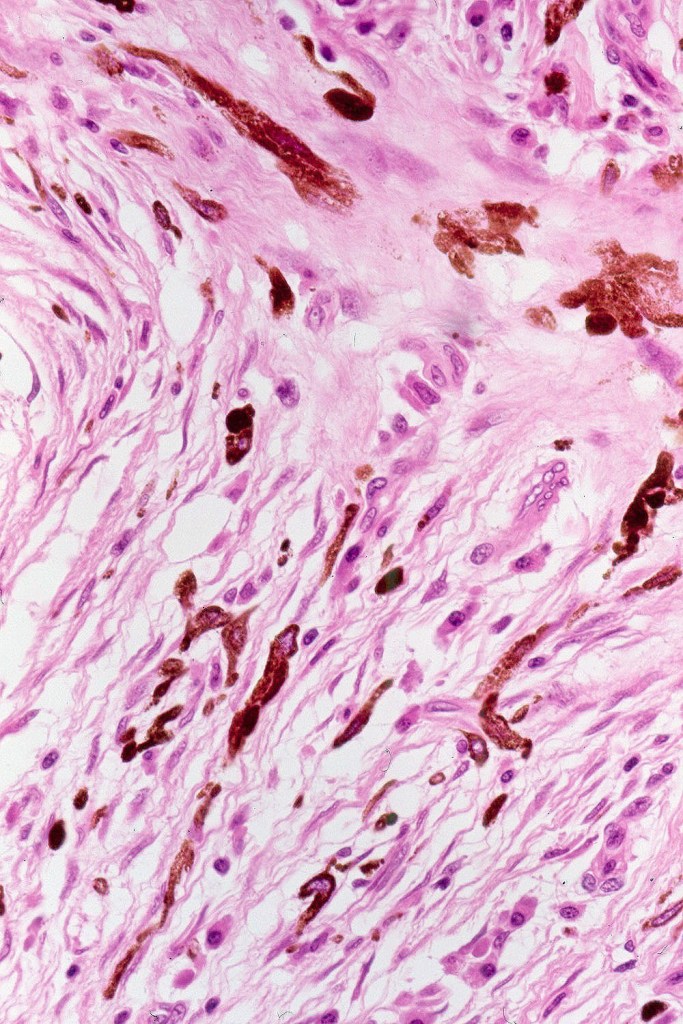

Histologically the features are very subtle and may require a Masson Fontanna stain or immunohistochemistry for diagnosis. Small numbers of dendritic melanocytes are present in the deep dermis siad to be orientated parallel to the epidermis.

Histologically, both lesions are characterized by the presence of denritic melanocytes in the upper & mid dermis. The overlying epidermis is often hperpigmented and increased numbers of melanocytes are sometimes evident.

Histologically, it is characterized by a dense population of spindled, dendritic melnanocytes & melanophages with variable fibrosis. It may sometimes represent a component of a combined nevus. Mitotic activity is not usually present and pleomorphism is absent (see atypical blue nevus below). Involvement of the arrector pili muscle is not uncommon.

•Admixture of spindle cells, pigmented bipolar or dendritic cells & melanophages

•Stromal fibrosis, myxoid change, vascular hyalinization with cyst formation are often seen